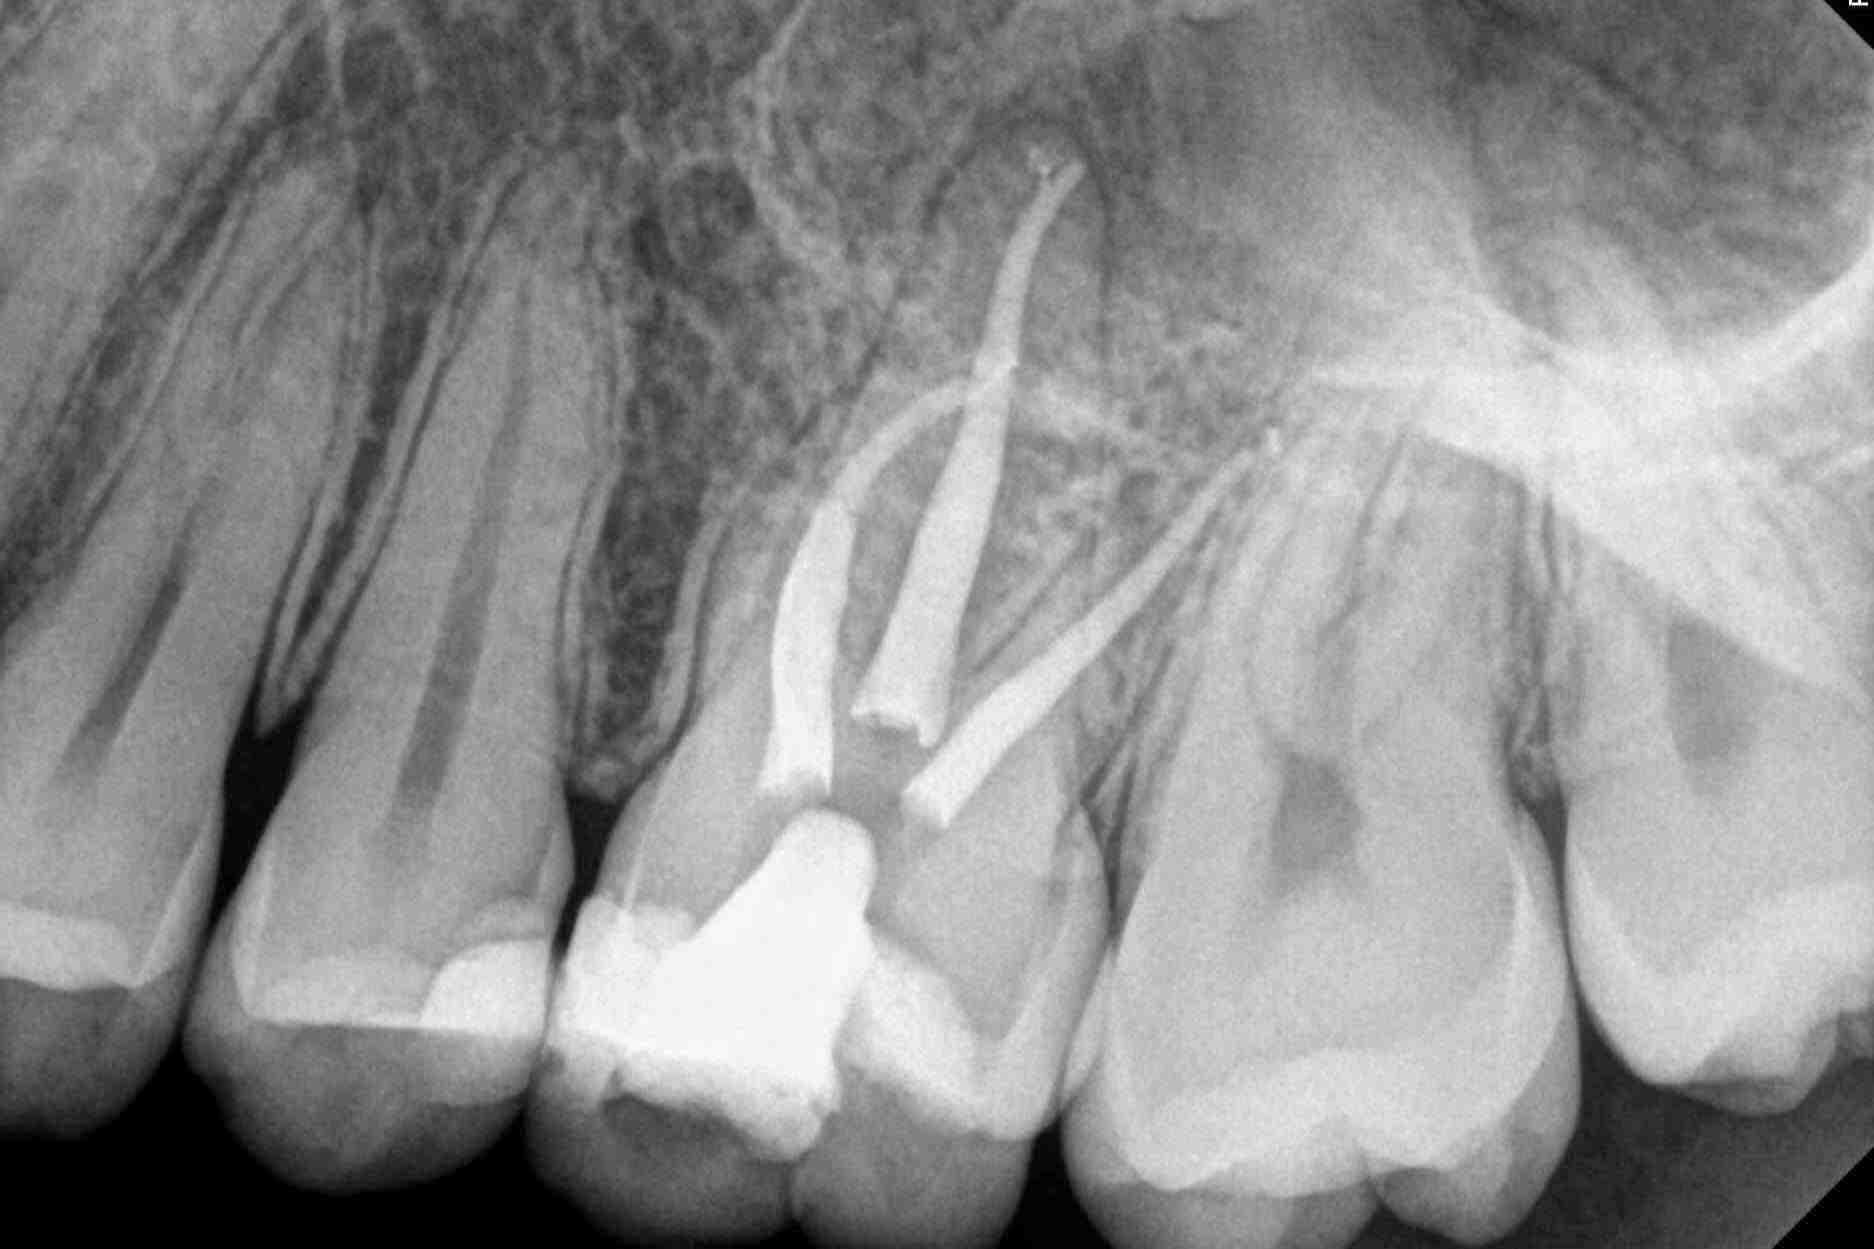

Tooth, Root, and Canal Anatomy Pocket Dentistry Can You Have Two Root Canals On The Same Tooth While most teeth typically have one to four root canals, certain teeth, like molars, can have multiple canals. Here are some tips for making them a success! After removing the canal filling, the endodontist can clean the canals and carefully examine the inside of your tooth using magnification and illumination, searching for any additional canals or unusual anatomy that requires. Can You Have Two Root Canals On The Same Tooth.

The anatomy of root canals. YouTube Can You Have Two Root Canals On The Same Tooth Root canal failure can occur within a few weeks. After removing the canal filling, the endodontist can clean the canals and carefully examine the inside of your tooth using magnification and illumination, searching for any additional canals or unusual anatomy that requires treatment. Root canal treatment is like any other medical or dental procedure. It presents challenges that many dental. Can You Have Two Root Canals On The Same Tooth.